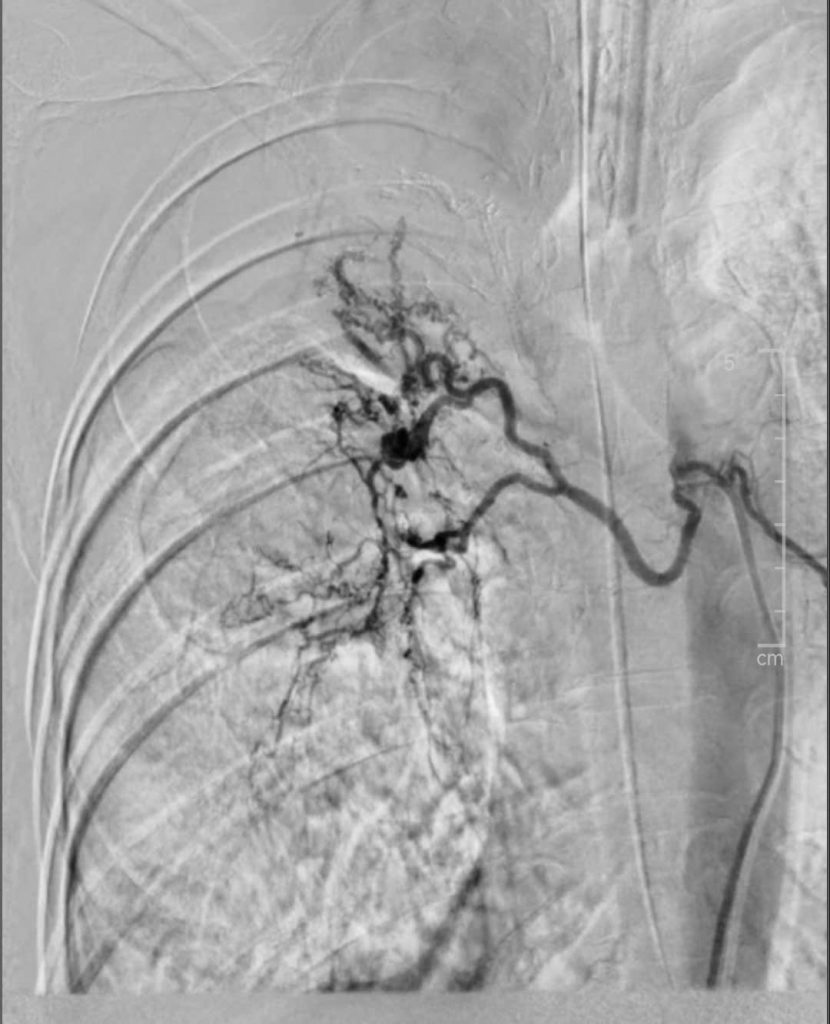

Hình ảnh sau can thiệp

Kết thúc ca can thiệp, lâm sàng bệnh nhân cải thiện dần, rút được ống nội khí quản, chuyển về khoa Nội Hô Hấp để tiếp tục theo dõi và dùng thuốc điều trị bệnh lý nền. Hiện tại, bệnh nhân không còn tình trạng ho ra máu, hồi phục tốt, có thể ăn uống và trở lại sinh hoạt bình thường, dự kiến xuất viện sớm.